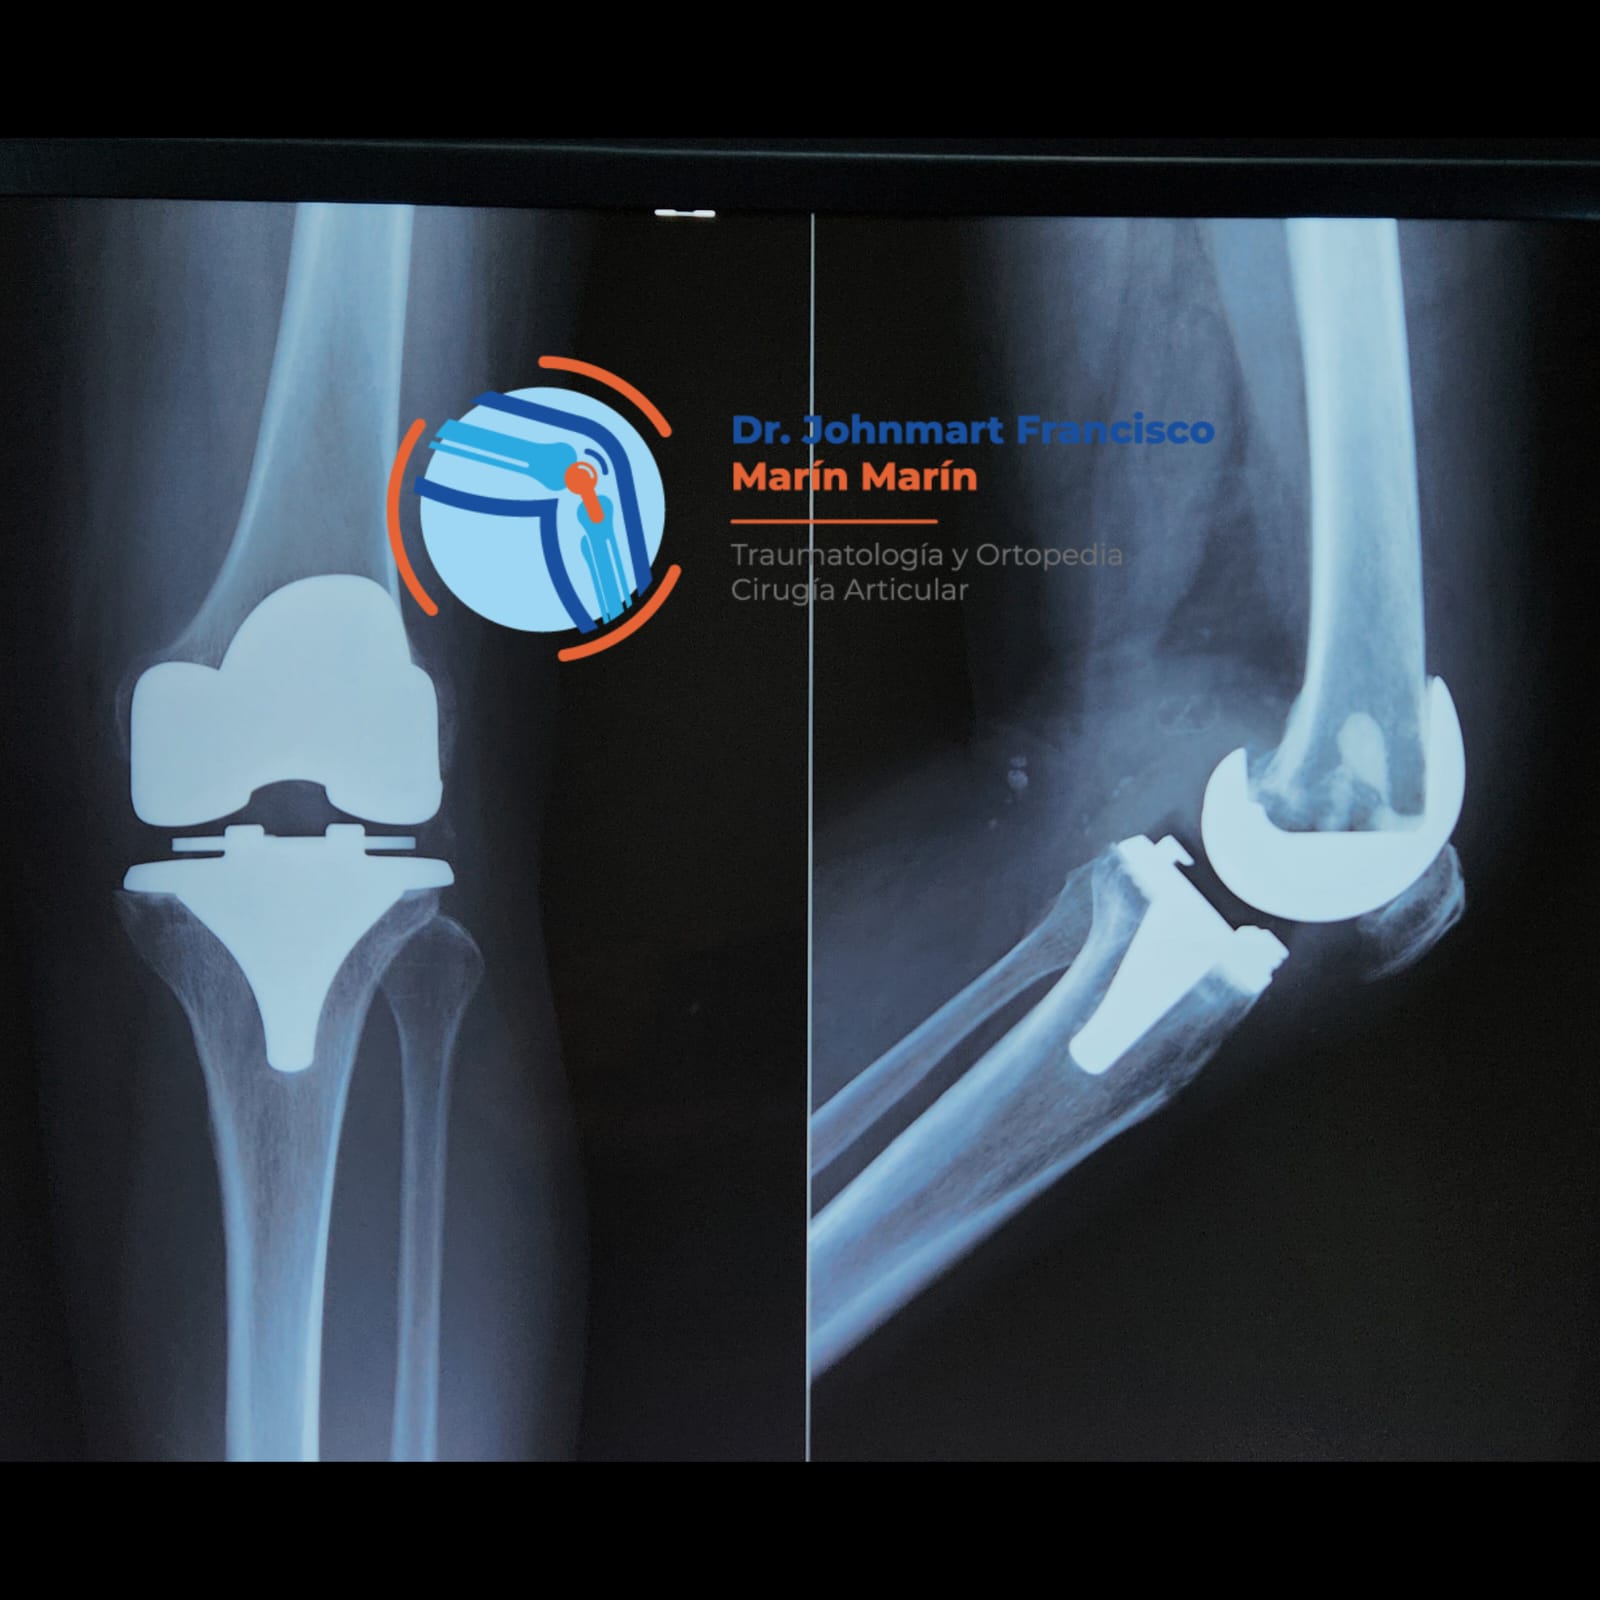

GONARTROSIS

Manejo especializado de Gonartrosis o artrosis de rodilla.